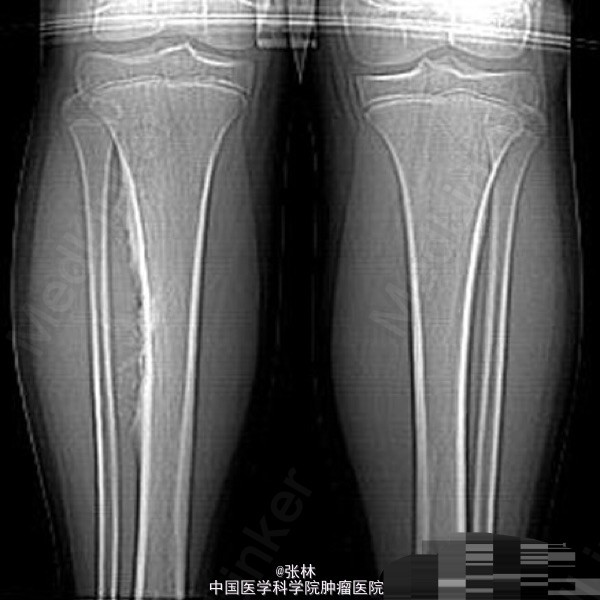

【病史临床】患者,女性,11岁,右侧胫骨上段触痛,血象及皮温不高。

影像表现:右胫骨外侧骨皮质表面低密度软组织肿块,与骨干长轴平行,基底部有条状钙化影,肿块边缘有骨膜新生骨,骨皮质内面未受侵犯,肿块与骨皮质间无透亮间隙。

术后病理结果:尤文氏肉瘤(IIb期)